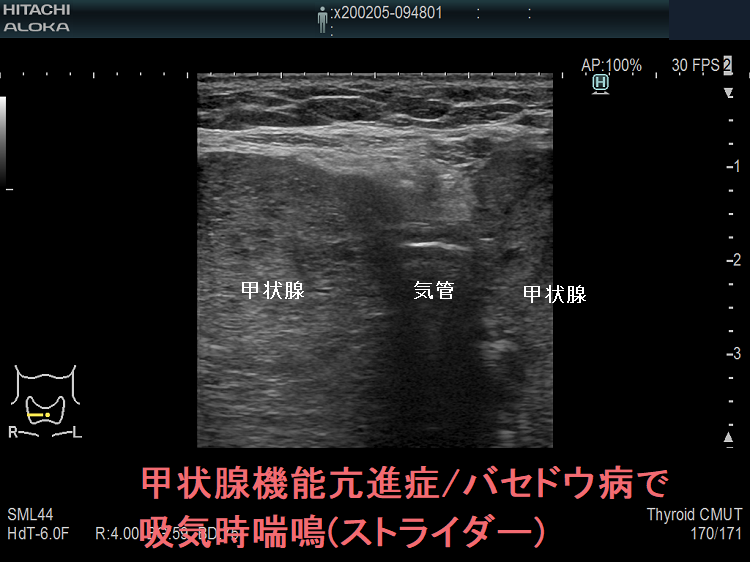

甲状腺機能亢進症/バセドウ病の巨大甲状腺腫による上気道狭窄で吸気時喘鳴(ストライダー;上気道・中枢気道狭窄による喘鳴)